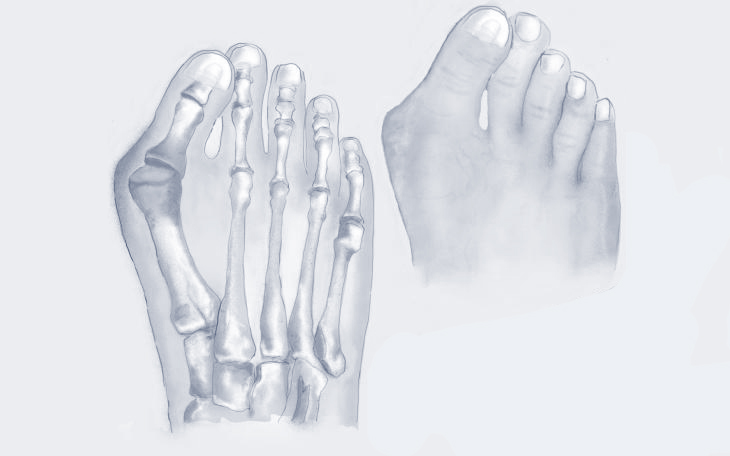

Erkrankungen des Vorfußes

Der Vorfuß trägt bei jedem Schritt einen Großteil des Körpergewichts und ist daher anfällig für Fehlstellungen, Überlastung und Verschleiß. In dieser Kategorie erhalten Sie einen Überblick über häufige Erkrankungen des Vorfußes, deren Ursachen, typische Symptome und bewährte Therapiemöglichkeiten.

Bildquelle: www.docset.de